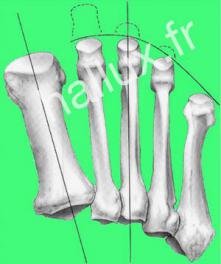

....une ostéotomie du deuxième métatarsien, selon la technique de Weil, souvent étendue au métatarsien adjacent voire aux autres métatarsiens latéraux selon leur forme et leur longueur, de façon à conserver une courbe harmonieuse.

Le but de cette ostéotomie et de corriger les troubles d'appui par un raccourcissement du métatarsien...

Elle peut être réalisée par technique conventionnelle, par voie mini-invasive ou percutanée, avec ou sans ostéosynthèse (vis).

Elle vise à redonner une courbe métatarsienne harmonieuse.